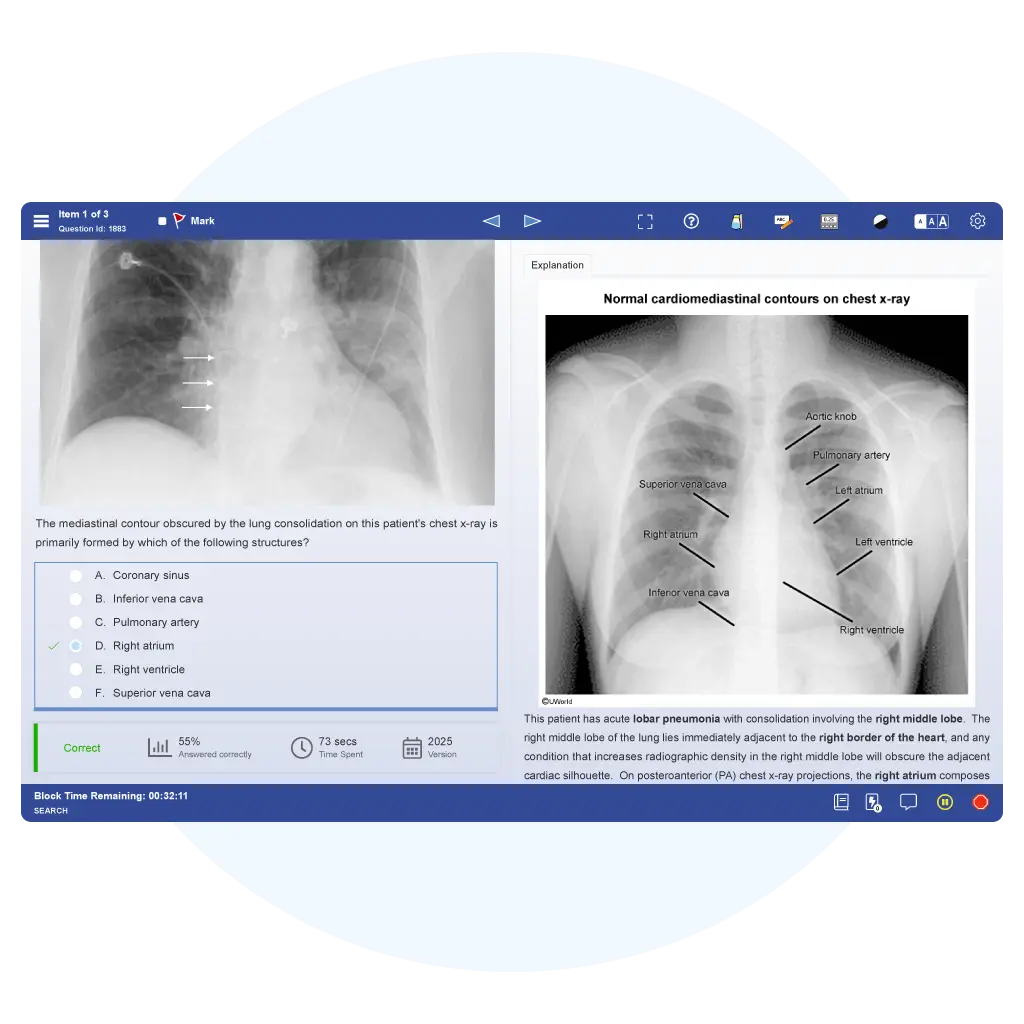

| Answer Explanations | Comprehensive, visually engaging, and fully teach concepts | More concise without as much high-yield content |

We offer thousands of exam-style questions for each exam that feature real-life scenarios you may experience in your career.

If we’re known for 1 thing, it’s our rationales. We fully explore topics and explain why answer options are correct or incorrect.